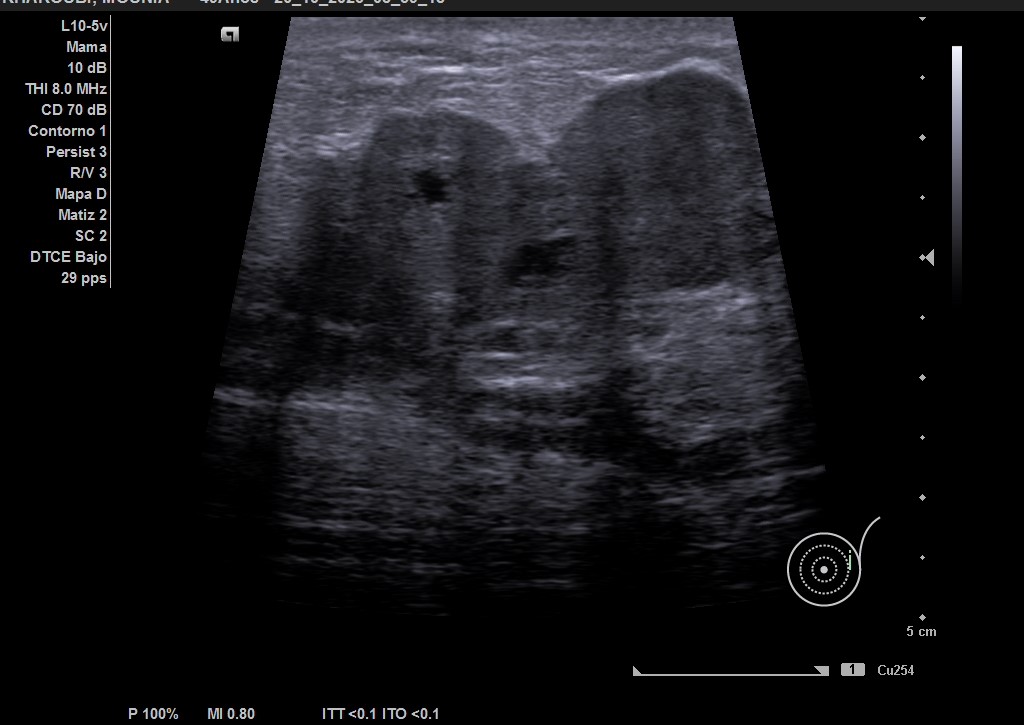

Hallazgos ecográficos

Ecografía: mama izquierda se observa tumoración hipoecogénica lobulada en cuadrante superior externo de aproximadamente 4 cm, heterogénea, que capta al Doppler color y dos adenopatías de aspecto reactivo en axila homolateral. Imagen sospechosa de malignidad.

Ecografía de mama hospitalaria: Se confirma en mama izquierda masa sólida palpable de al menos 56 mm, de contorno mal definido, sospechosa de malignidad. Se realizará BAG ecoguíada, y adenopatías axilares izquierda de aspectos patológico. PAAF de ganglio izquierdo dirigida por ecografía: Citología positiva para malignidad. Compatible con metástasis de carcinoma. Biopsia BA Tipo histológico: Carcinoma infiltrante. Grado histológico: Grado III, pobremente diferenciado.